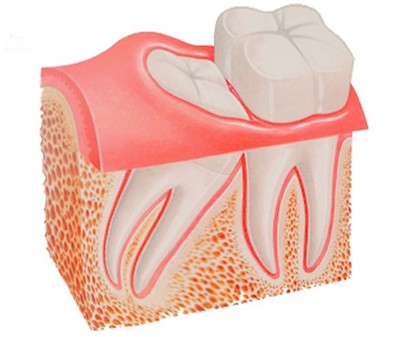

La pericoronaritis es una infección buco-dental de los tejidos blandos de la boca, más concreto, la encía que rodean un diente cuando en su proceso de erupción, queda parcialmente cubierto. Se suele desarrollar de forma general durante la erupción de los terceros molares, también llamados «Muelas Del Juicio»

1.- Debido a que la erupción del tercer molar no se puede dar de manera natural y los dientes quedan retenidos y/o impactados.

Inflamación de la encía que cubre la corona del Tercer Molar

Infección de la zona adyacente al diente que está erupcionando